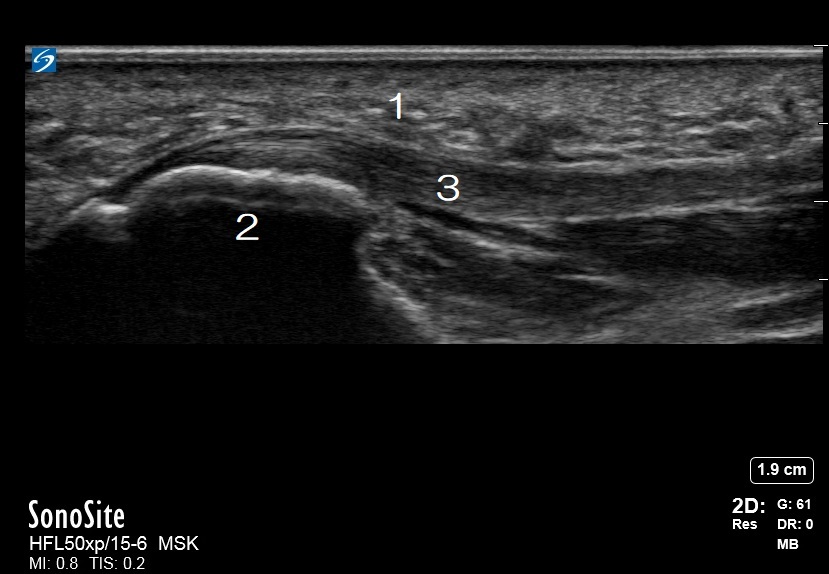

Foot & Ankle Plantar Fascia 1 Image

Fat Pad of the Heel

Calcaneus

Plantar Fascia